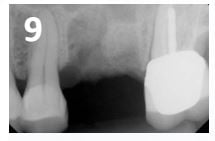

• Immediate post-operative radiograph illustrates correct placement of the OsteoGen® Plug. The site will be allowed to integrate for approximately 4 months prior to dental implant placement. The site will show radiolucent on the day of placement and radiopaque as the graft is resorbed and replaced by bone.(Fig. 9)